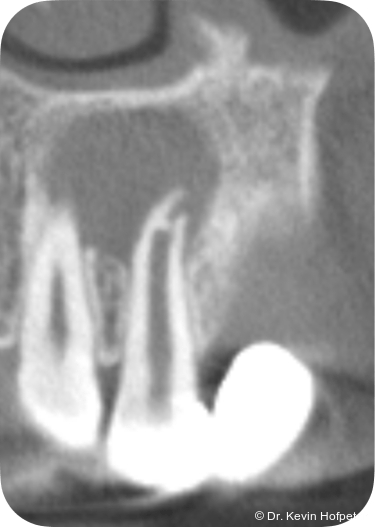

Zwei Monate später konnte die definitive Obturation erfolgen. Da der Kanal nun trocken war, konnte die Dentinbrücke im apikalen Bereich unter Sicht entfernt werden (Abb. 3). Das Mineral Trioxid Aggregat (MTA, Medcem) wurde frisch mit steriler Kochsalzlösung angemischt und mithilfe einer MTA-Gun (MAP-System, Produits Dentaires) sowie individuell angepassten Guttaperchastiften in den gekrümmten Kanalabschnitt eingebracht. Die größte technische Herausforderung bestand im Einbringen eines dichten apikalen MTA-Verschlusses hinter der Kurvatur (Abb. 4). Nachdem dieser Verschluss gesetzt war, wurde der restliche Kanal mit einem Epoxidharz-Sealer (AH Plus, Dentsply Sirona) und erwärmter Guttapercha mittels warm-vertikaler Kompaktion gefüllt und der Zugang adhäsiv verschlossen (Abb. 5).